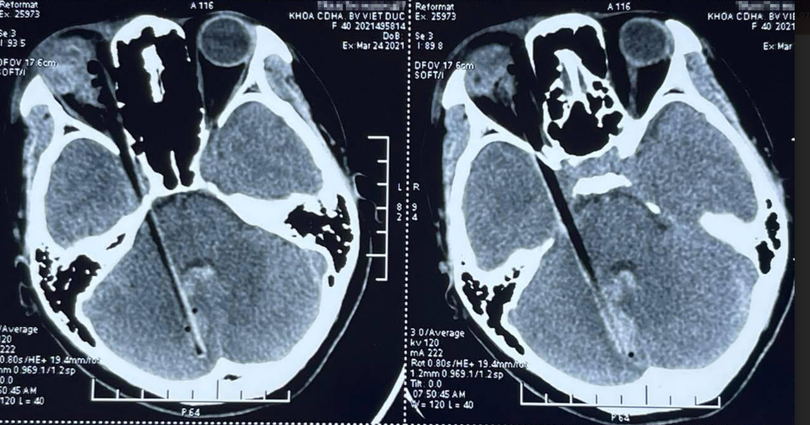

Hình ảnh dị vật đâm xuyên qua hốc mắt, vào sọ não của bệnh nhân (Ảnh - BVCC) |

Tại Bệnh viện Hữu nghị Việt Đức, các bác sĩ đã khám và chụp chiếu phát hiện hốc mắt của chị H. có dị vật là một mảnh gỗ dài, cắm vào thành trong hốc mắt. Mảnh gỗ này đã đi qua sát vùng xoang hang đến tận hố sọ sau rồi cắm vào tiểu não phải, sát thân não khiến bệnh nhân bị tổn thương, chảy máu.

Sau nhiều giờ căng thẳng, TS. Lê Hồng Nhân cùng nhóm phẫu thuật viên thần kinh đã lấy được mảnh gỗ dài thuôn nhọn ở đầu dài gần 12cm, dày 0,5cm cắm thành vào thành xương sọ của bệnh nhân.